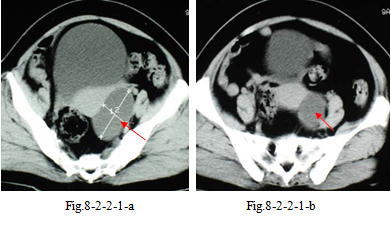

1.患者女性,52 岁。主诉:查体B 型超声发现附件囊肿。妇科内诊:子宫增大,质中,左侧可扪及150px×125px×125px大小肿物。CT盆腔平扫(Fig.8-2-2-1-a~b)示:左侧卵巢囊肿(左侧附件区100px×175px 囊性低密度,边缘光整)。手术:左侧卵巢有约150px×125px大小囊肿,表面光滑透明。术后病理:左侧卵巢多房性浆液性囊腺瘤。经验教训:CT平扫未能显示囊肿内存有间隔,而误为单纯囊肿。